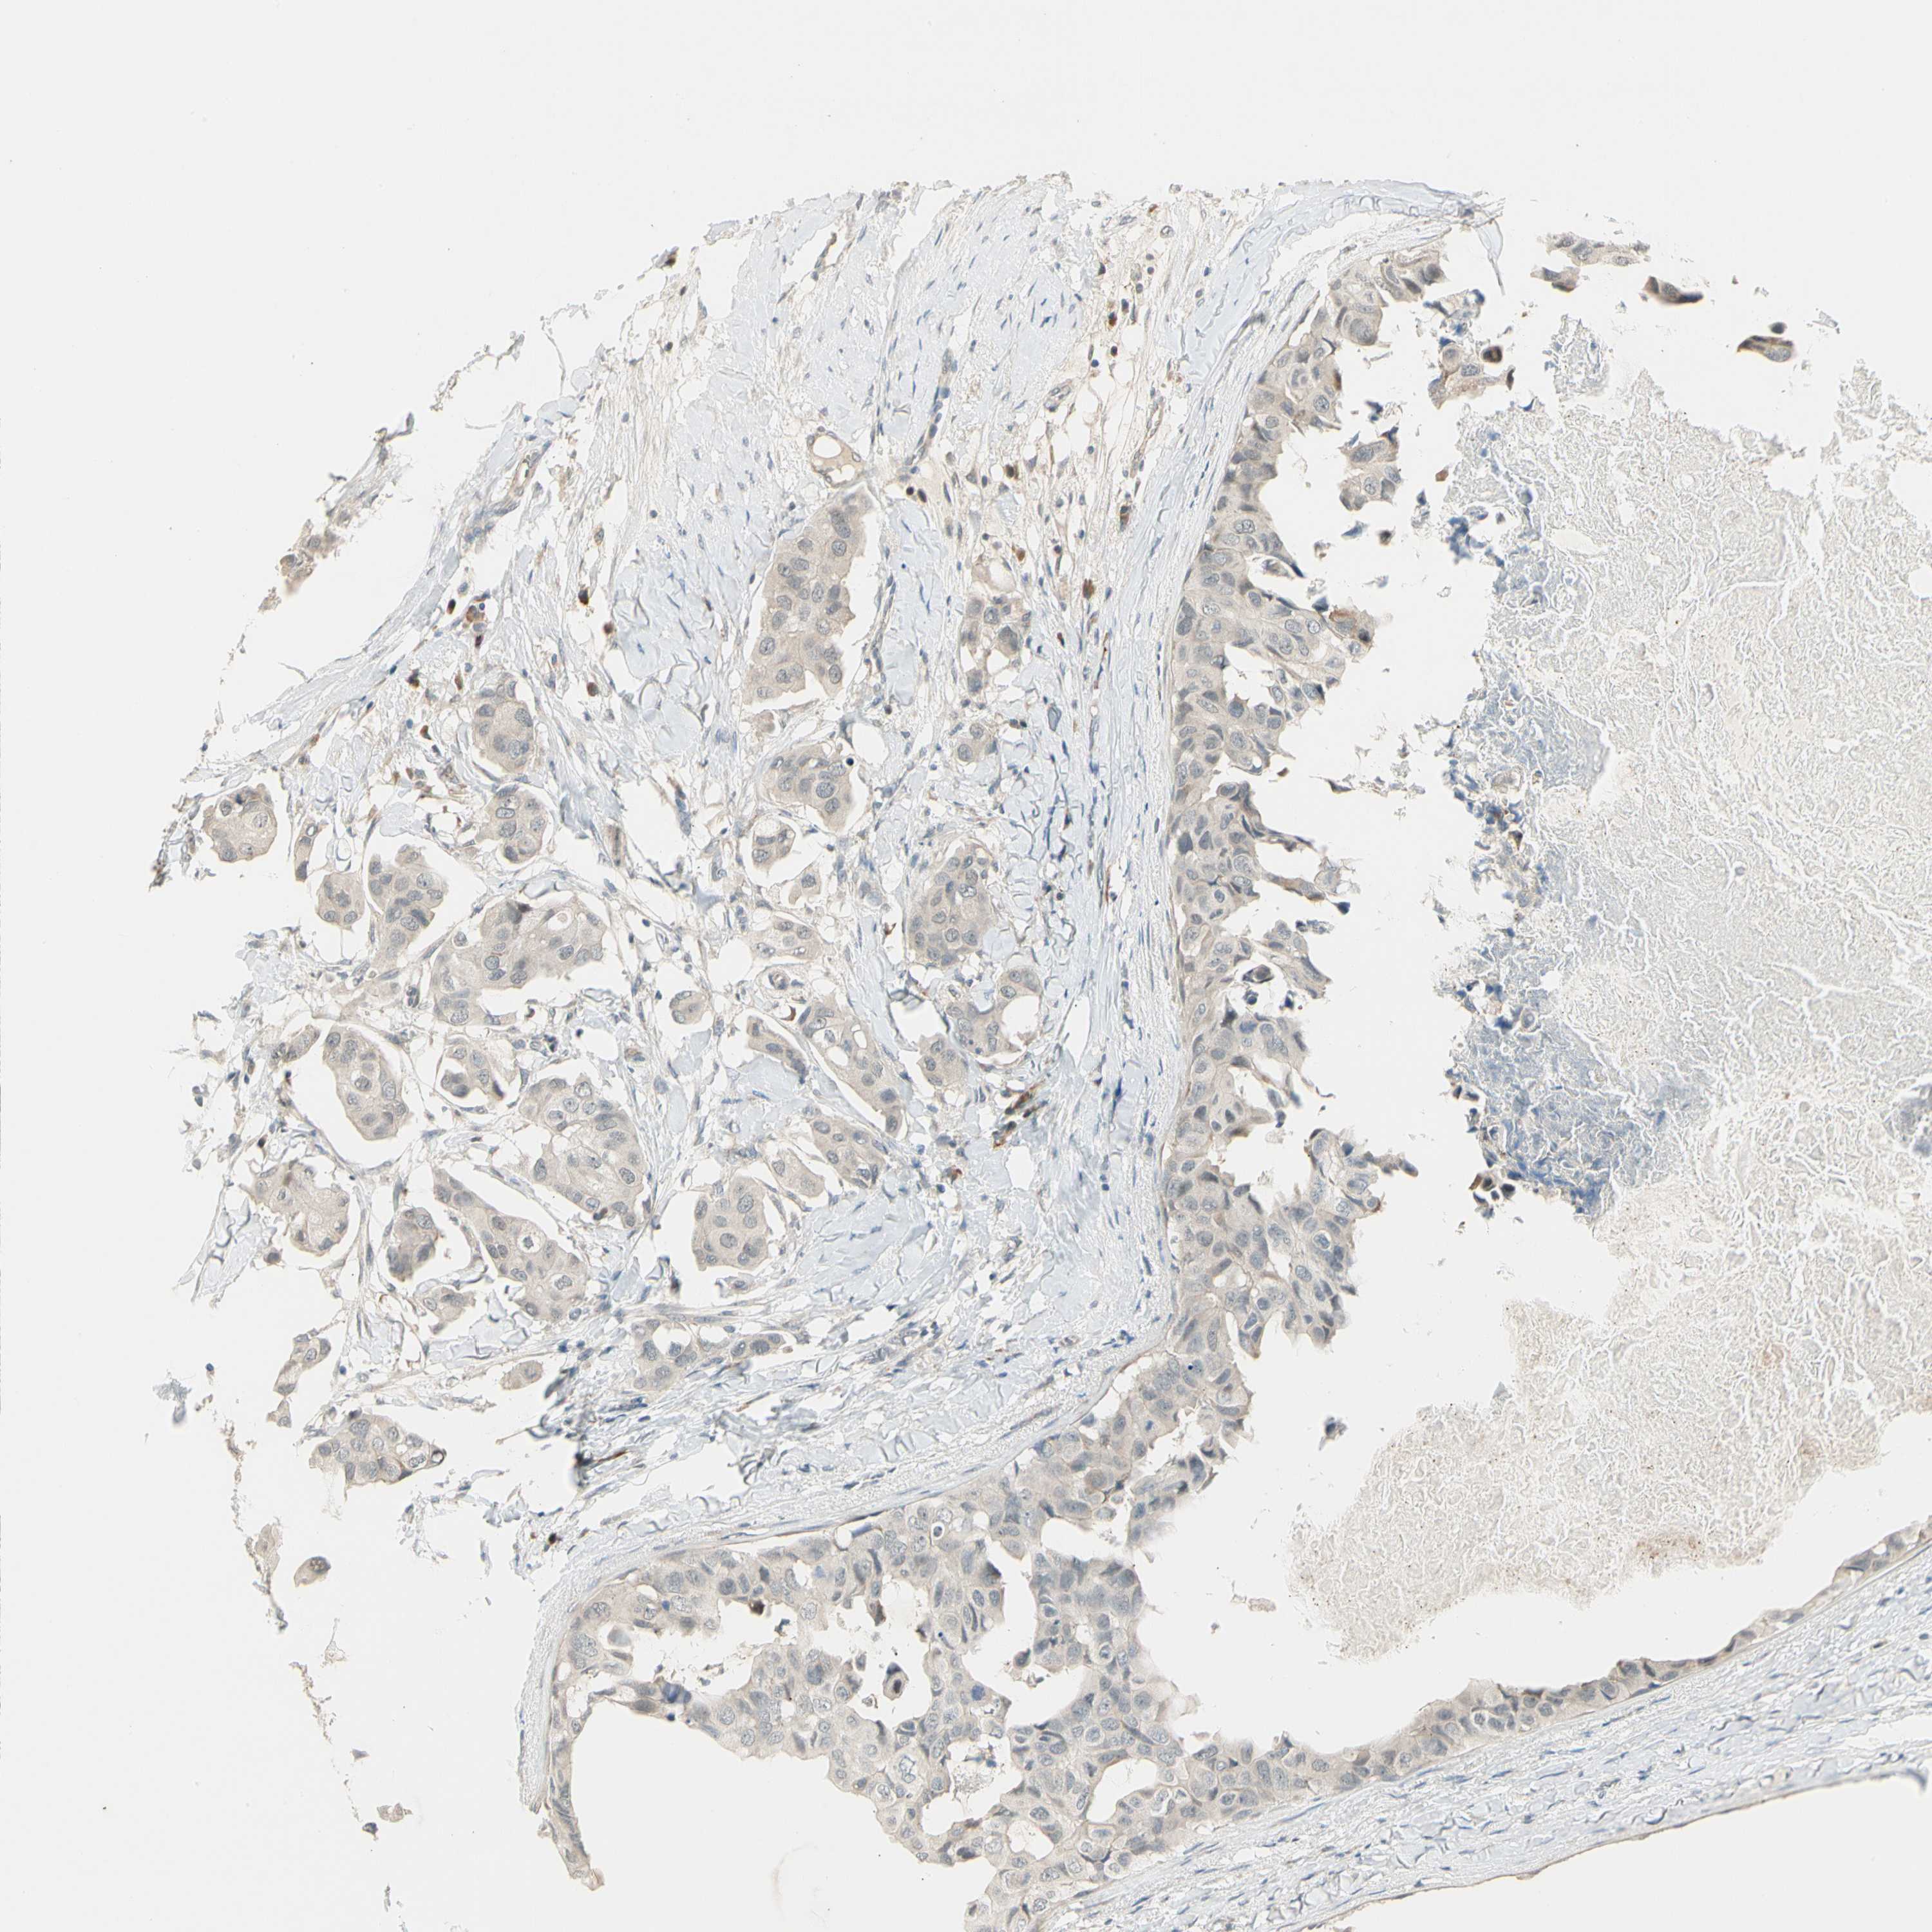

BRCA TCGA BRCA VALIDATION PROTEIN EXPRESSION